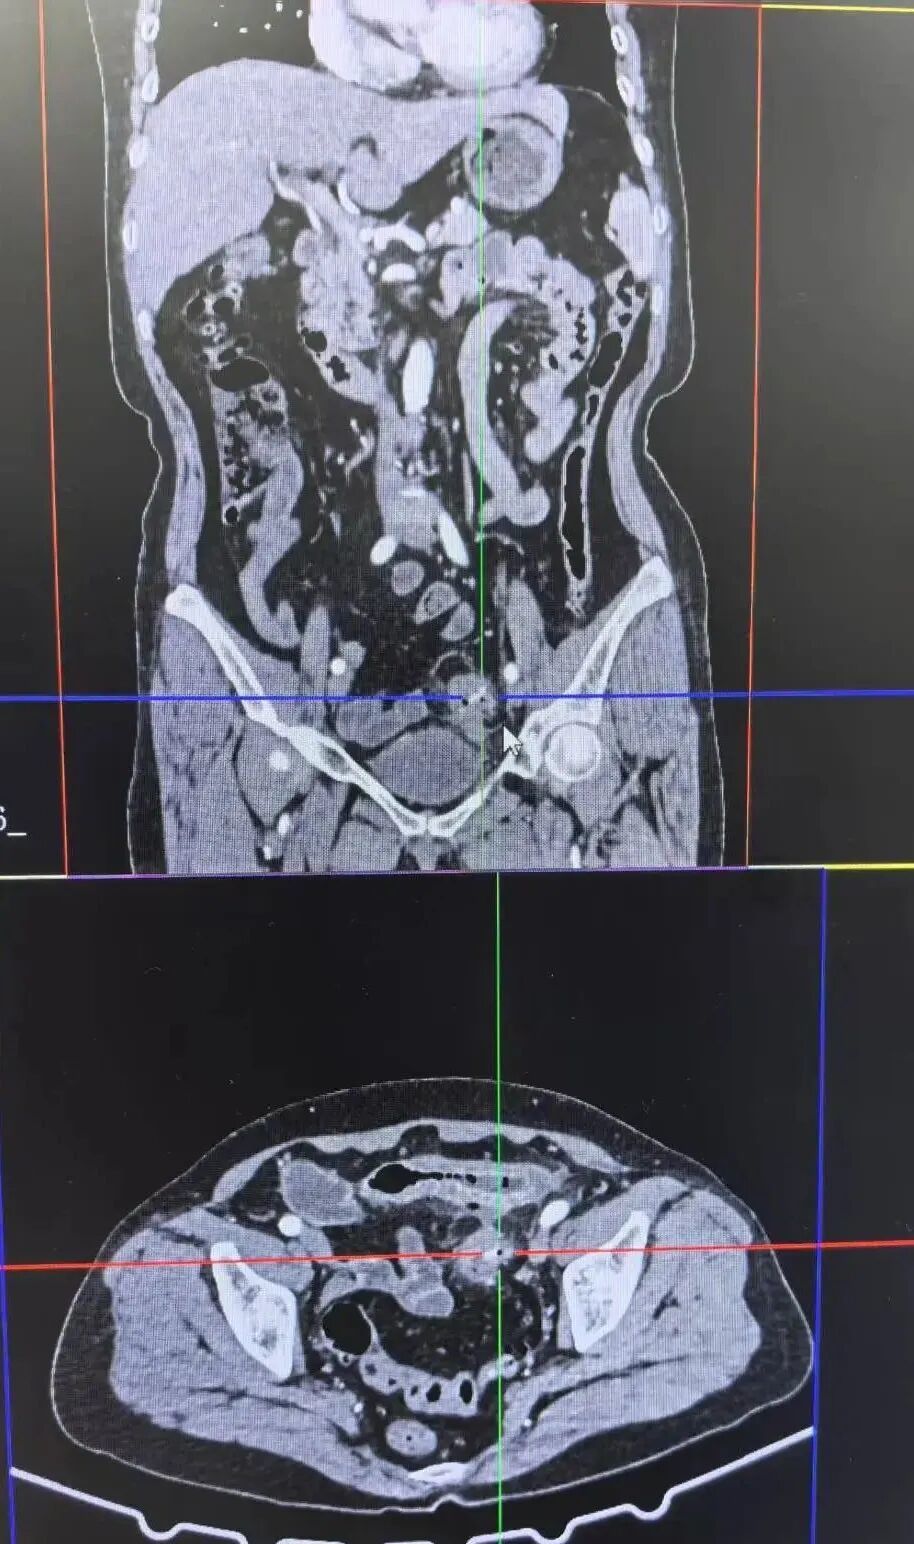

病因是什么?李阿姨和家人都很茫然,既往没有任何疾病,也没吃辛辣刺激、油腻的食物。直到赵伟主治医师反复追问饮食史,她才想起,2天前她吃过鱼,但她认为没有吞下骨头或鱼刺。医生急查CT发现,乙状结肠周围有大量的腹腔游离气体,说明肠道已穿孔。

病情危急,必须立刻手术。可异物藏在肠子里面,从外面很难找到。为此,普外科周亮主任开展了多学科协作方案,周亮主任团队先通过腹腔镜从外部寻找,消化内科的肠镜设备就在手术室待命,准备随时从肠道内部进行探查,确保万无一失。